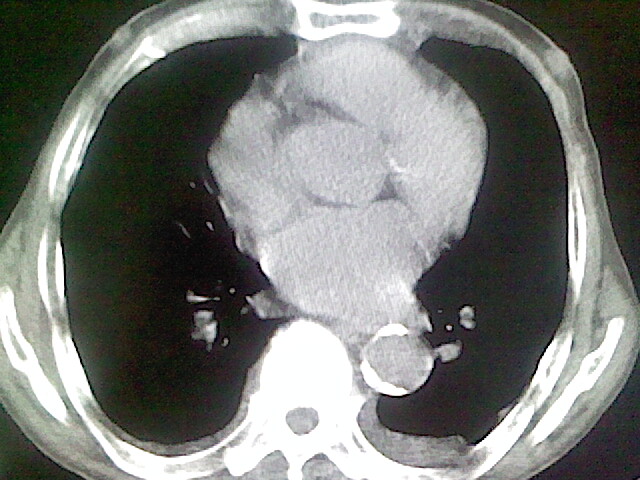

以下是引用zsl6918在2008-8-28 16:49:00的发言:[br]双肺炎性病灶,食管狭窄估计与心房增大压迫所致。

以下是引用xulianj在2008-8-28 20:36:00的发言:[br]慢支肺气肿伴感染,右上肺陈旧性结核;食道建议胃镜检查。

以下是引用wqs571018在2008-8-28 21:18:00的发言:[br]慢支继发感染,右上肺陈旧性结核;食道建议胃镜检查。